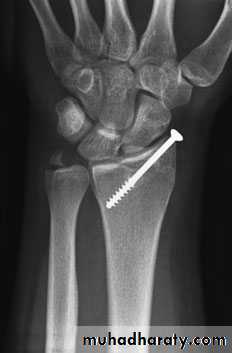

3-IMPACTED OR COMMINUTED COLLES’ FRACTURESWith substantial impaction or comminution in osteoporotic bone, manipulation and plaster immobilization alone may be insufficient. The fracture can sometimes be reduced and held with percutaneous wires, but if impaction is severe even this may not be enough to maintain length; in that case, an external fixator is used to neutralize the compressive force of the 25 tendons crossing the wrist, and bone graft or bone substitute is placed into the gap. The fixator is attached to the distal radius and the second metacarpal shaft.

IMPACTED OR COMMINUTED COLLES’ FRACTURES